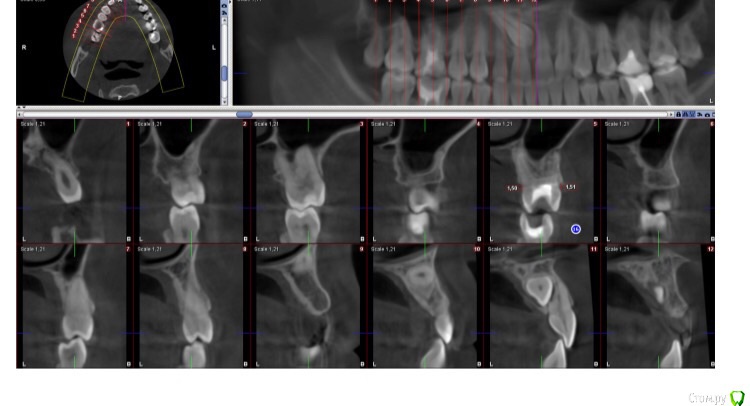

Jason Fa Опубликовано 6 мая, 2015 Автор Поделиться Опубликовано 6 мая, 2015 Вот как лежал клык Ссылка на комментарий